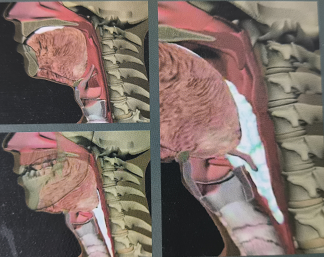

本圖來源于醫(yī)療用書《吞咽障礙評估與治療》,版權歸原作者所有

吞咽障礙是由于下頜、雙唇、舌、軟腭、咽喉、食管等器官結(jié)構(gòu)和(或)功能受損,不能安全有效地把食物送到胃內(nèi)取得足夠營養(yǎng)和水分的進食困難。

FEES為吞咽障礙診斷的“金標準”之一,通過纖維喉內(nèi)鏡吞咽評估可了解鼻咽部、喉部和粘膜改變,直接觀察患者咽喉部的分泌物,評估咽喉部感覺,評估進食時食團運送和氣道保護、聲門閉合和食團清除等情況。